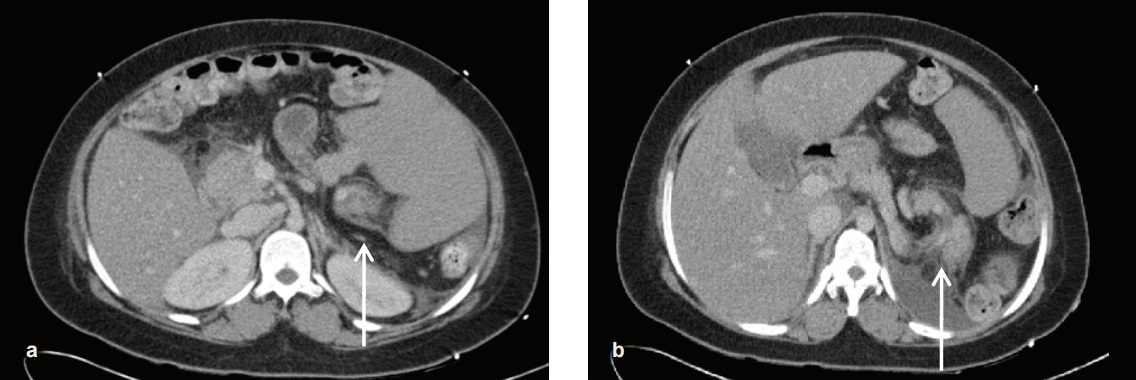

A wandering spleen is a rare disorder with the incidence in a general population of less than 0.2%.13 A wandering spleen can be congenital or acquired. The congenital cause is due to absence or weakness of ligaments holding the spleen. In these cases, the spleen is held by a vascular pedicle instead of ligaments. The blood vessels in the vascular pedicle can be blocked leading to ischaemia and infarction of the spleen. Acquired wandering spleen is due to weakness of the ligaments such as in pregnancy14 and abdominal wall laxity. Usually, this is found in males under 10 years old, or females at 20-40 years old when they present with splenic torsion.6,15 A wandering spleen presents in a variety of manner from asymptomatic to an acute abdomen.16 The complications associated with a wandering spleen include gastric obstruction, spleen infarction and recurrent pancreatitis.17 A wandering spleen is associated with splenomegaly. The classic "whirl" appearance represents the twisted splenic pedicle signifying a torted spleen.18 In this case, the pancreatic tail was involved because it was entrapped in the twisted splenorenal ligament during spleen torsion. This led to acute pancreatitis possibly because of pancreatic ischaemia or folding of the main pancreatic duct.19,20

Click here to download Figure 2Figure 2. Torsion of patient's wandering enlarged spleen, with "whirling" of spleen (white arrow in picture A) and involving the pancreatic tail (white arrow in picture B).